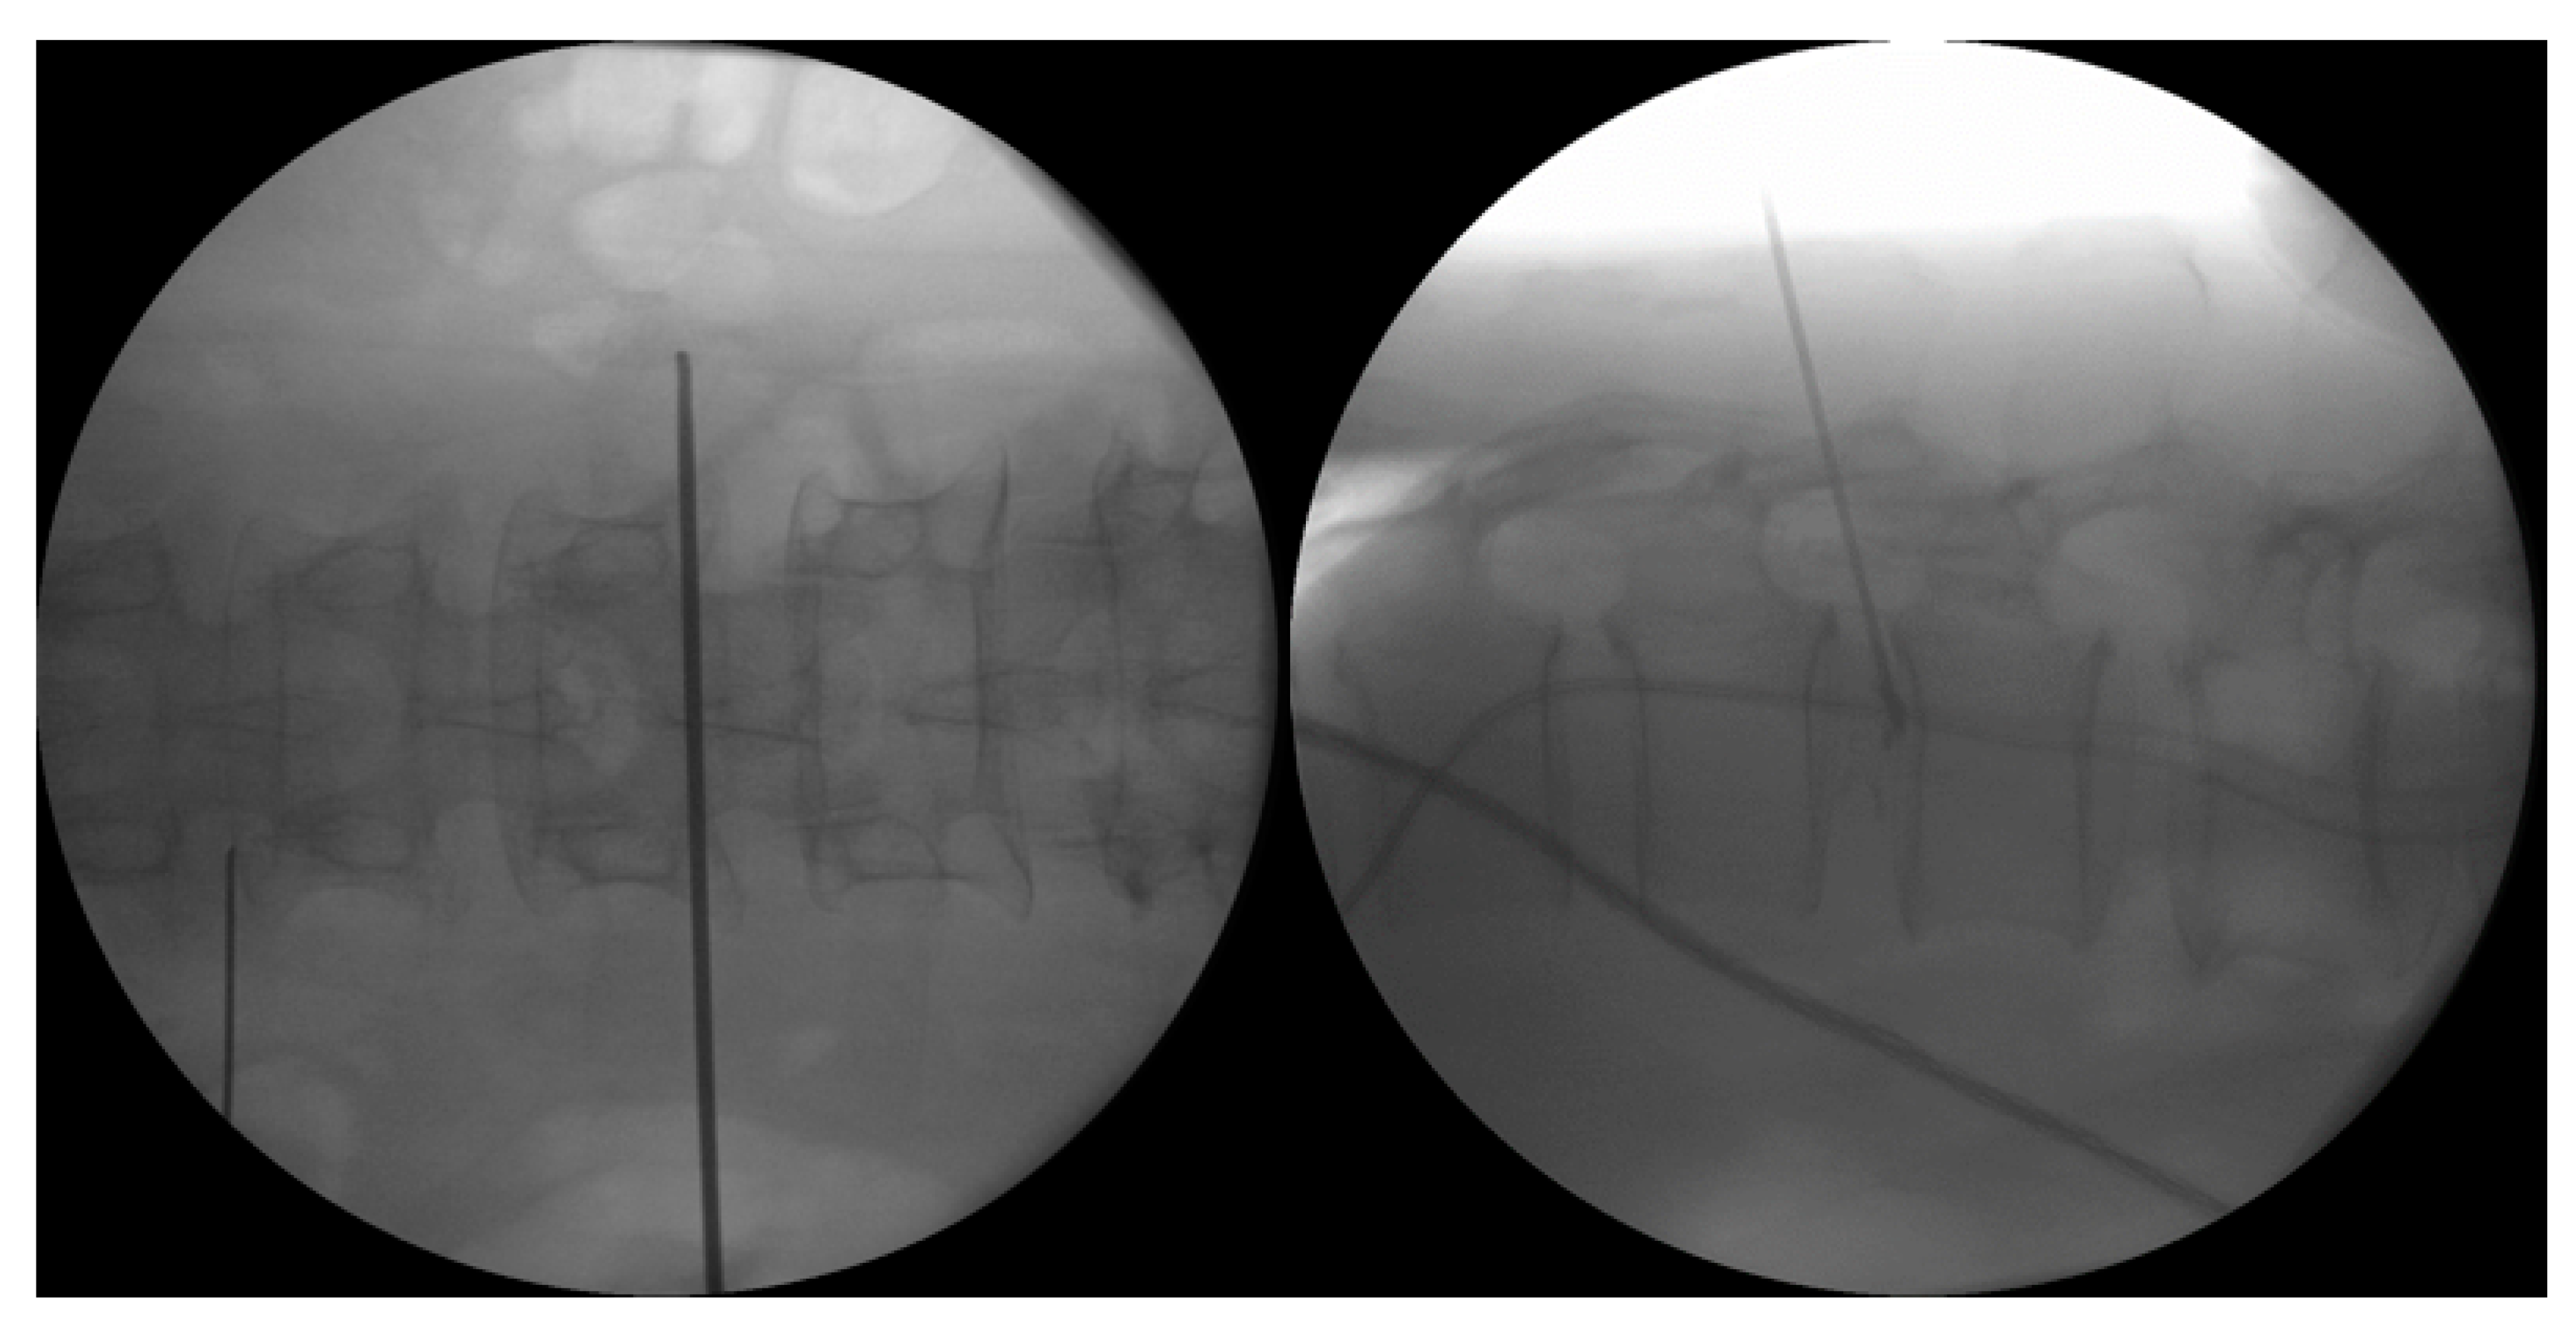

4.1.1. Interlaminar Endoscopic Lumbar Approach to Disc

4.1.2. Lumbar Endoscopic Unilateral Laminotomy for Bilateral Decompression with Radiofrequency Ablation

4.1.3. Transforaminal Endoscopic Lumbar Approach for Radiofrequency Ablation

4.2. Ablation of Neuropathic Basivertebral Nerve and Sinuvertebral Nerve